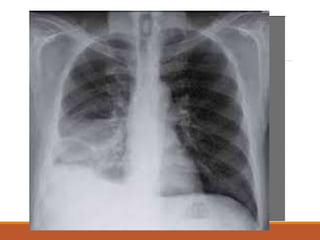

IMAGENOLOGÍA

Rx. Tórax:

Presentan alteraciones en el 50% de

los afectados:

• infiltrado basal.

• derrame pleural.

• atelectasias planas.

• elevación del hemidiafragma

derecho.